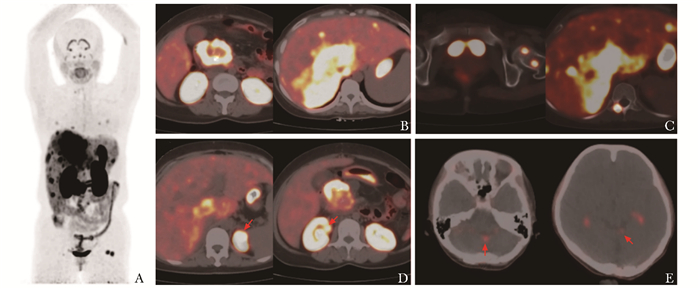

• 摘要: VHL(von Hippel-Lindau)综合征是一种罕见的常染色体显性遗传病。其临床表现复杂且多样,主要表现为视网膜、中枢神经系统、肾脏、胰腺等部位的多发肿瘤,患者常需进行全身多脏器评估。碳酸酐酶Ⅸ在VHL相关病变中普遍表达,68Ga-NY104作为一种新型小分子示踪剂,可对碳酸酐酶Ⅸ阳性病灶进行全身成像。本文报道一例32岁女性VHL综合征患者,先后行18F-FDG PET/CT和68Ga-NY104 PET/CT评估病灶,结果发现后者在更多种类的病灶(包括肾脏、胰腺、肝转移病灶及小脑病灶)中存在摄取。本文就该患者相关病灶的评估过程展开讨论,以期为探索VHL综合征患者的“一站式”评估手段提供借鉴。

Abstract: VHL (von Hipple-Lindau) syndrome is a rare autosomal dominant genetic disease with complex and diverse clinical manifestations, which primarily presents as multiple tumors in the retina, central nervous system, kidneys, pancreas, and other areas. Patients often require comprehensive multi-organ assessment. Carbonic anhydrase Ⅸ (CAⅨ) is ubiquitously expressed in VHL-related lesions, and 68Ga-NY104, a novel small-molecule tracer, can perform whole-body imaging of CAⅨ-positive lesions. This case report introduces a 32-year-old female patient with VHL syndrome who underwent sequential 18F-FDG PET/CT and 68Ga-NY104 PET/CT for lesion assessment. Notably, 68Ga-NY104 PET/CT demonstrated uptake in a broader range of lesions (including renal, pancreatic, hepatic metastatic lesions and cerebellar lesions). This article discusses the process of evaluating the relevant lesions in this patient, with the aim of exploring a "one-stop" evaluation tool for patients with VHL syndrome.